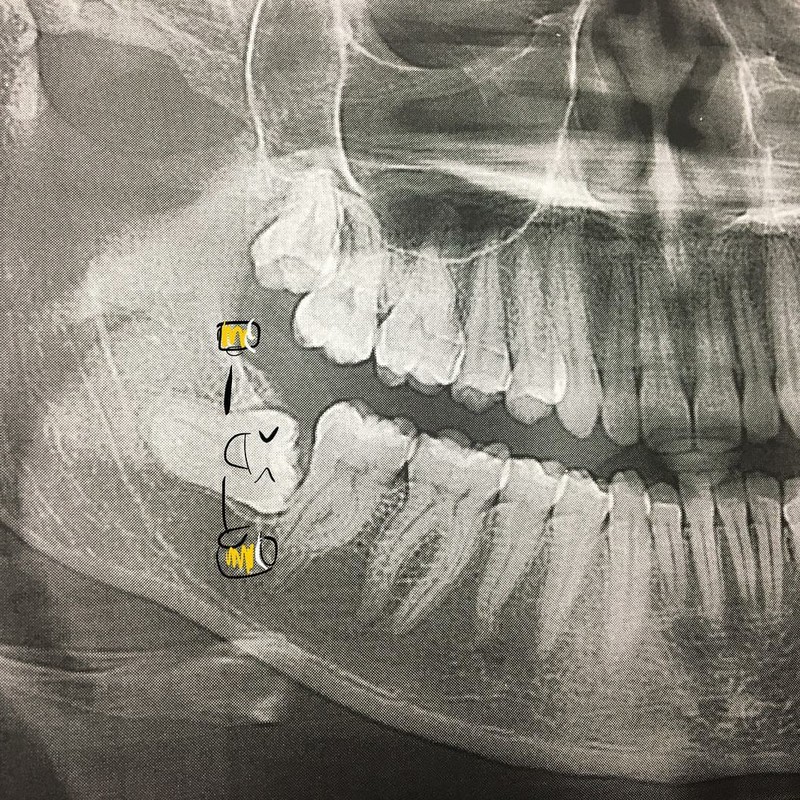

Ada yang aneh dengan struktur tulang pasien ini? Ya, Bentuknya mirip burung onta. (Foto: Instagram/radiologic_technologist)